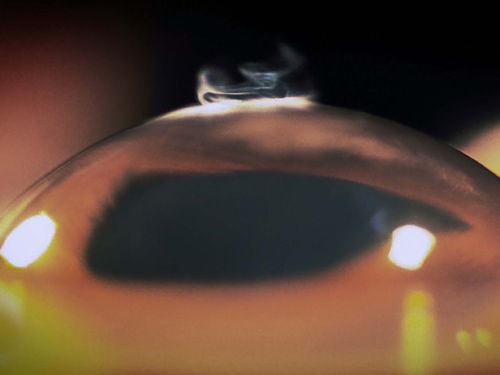

4.眼内晶状体上的硅油

眼内晶状体上的硅油

视网膜脱落的发病率大约在万分之一左右,视网膜——眼睛后面的光敏膜——脱离支撑层。这种疾病会导致视力下降或者失明。为了稳定视网膜,医生在患者眼睛上滴硅油。硅油有时会乳化,附着在植入眼睛的人造晶体上。